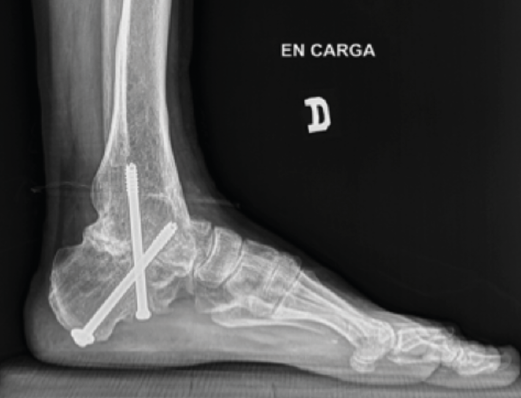

Figura 15. Control posquirúrgico tras la corrección de la pseudoartrosis en varo.

Utilidad de la impresión 3D: se decidió imprimir una guía 3D de corte como ayuda intraoperatoria. La guía permite la resección de la coalición de manera completa y reducir la necesidad de guía con fluoroscopia.

Pasos:

- Obtención de las imágenes (Figura 10).

- Identificación del plano de pseudoartrosis (Figura 11).

- Diseño de la guía de corte guiada por aguja de Kirschner (Figura 12).

- Colocación de la guía intraoperatoria sobre relieves óseos (Figura 13).

- Resección intraoperatoria (Figura 14).

- Control posquirúrgico tras la corrección de la pseudoartrosis en varo (Figura 15).